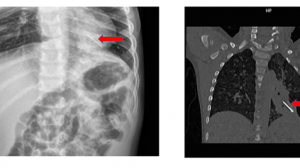

Ngày 22/8/2021 Khoa Cấp cứu – Bệnh viện Nhi Đồng Thành Phố tiếp nhận một trường hợp trẻ B. Đ. Th. Đ. 2 tuổi, nam ngụ ở Cần Giuộc, Long An, được chuyển từ bệnh viện địa phương với chẩn đoán ngạt nước do té ao. Khai thác bệnh sử ghi nhận sáng cùng ngày nhập viện, Đ. đang ở chơi trong nhà với mẹ, nhân lúc mẹ bé dọn dẹp nhà cửa không để ý đến, trẻ đi ra trước nhà chơi, không may té xuống ao nuôi cá, nước phía trước nhà. Người nhà phát hiện, vớt trẻ lên, xốc nước và đưa trẻ đến bệnh viện địa phương trong tình trạng hôn mê, tím tái thở yếu, co gồng, được các bác sĩ cấp cứu đặt nội khí quản giúp thở, chống co giật, sau đó chuyển đến Bệnh viện Nhi Đồng Thành Phố. Tại đây, ghi nhận trẻ hôn mê, tím tái, co gồng từng cơn, bọt hồng trào ra nội khí quản, Xquang ngực cho thấy phổi trẻ tổn thương nặng lan tỏa 2 phế trường, nên được xử trí thở máy thông số thích hợp, truyền thuốc vận mạch, chống co giật, chống phù não, điều chỉnh nước điện giải, kiềm toan và cho kháng sinh phổ rộng điều trị viêm phổi hít. Hiện tình trạng trẻ còn nặng, được chuyển Khoa Hồi sức tích cực điều trị tiếp.